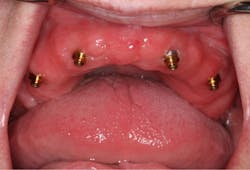

Fixed implant-supported bridges are becoming more prevalent worldwide. There are multiple types of bridges available, but all are expensive, and they require advanced clinical skills. Although these fixed bridges are a wonderful service to offer, we should remember the value of removable implant-retained dentures (figure 1). Attachments, such as Locator by Zest and Equator by Rhein83, have many benefits. They are the most affordable, least complicated, easiest to repair, and easiest to clean full-arch implant option.

Tip no. 3: Use more implants

It is widely noted that a minimum of two implants are required in the mandible for removable dentures.5 Four or more implants are optimal for the maxilla.6 These minimums can be successful more than 85% of the time, but long-term success can be increased by adding additional implants (figure 4).7 Balaguer et al. studied 95 patients over an average of six to nine years and found that survival rate in the maxilla of four implants was 85.7%. Survival rate of six implants was 100%. In the mandible, survival rate of two implants was 96.6%, whereas survival rate for three implants was 100% and survival rate for four implants was 99%.7

Adding additional implants reduces stress on each individual implant. In most cases, it helps ensure that if an implant is lost, there will be enough remaining implants for a successful case. In the mandible, additional implants will increase retention and, therefore, patient satisfaction. We offer financial incentives for our patients to add additional implants. It’s a win-win. Our patients enjoy greater security and success, and we invest less clinical time on adjustments and addressing complications.